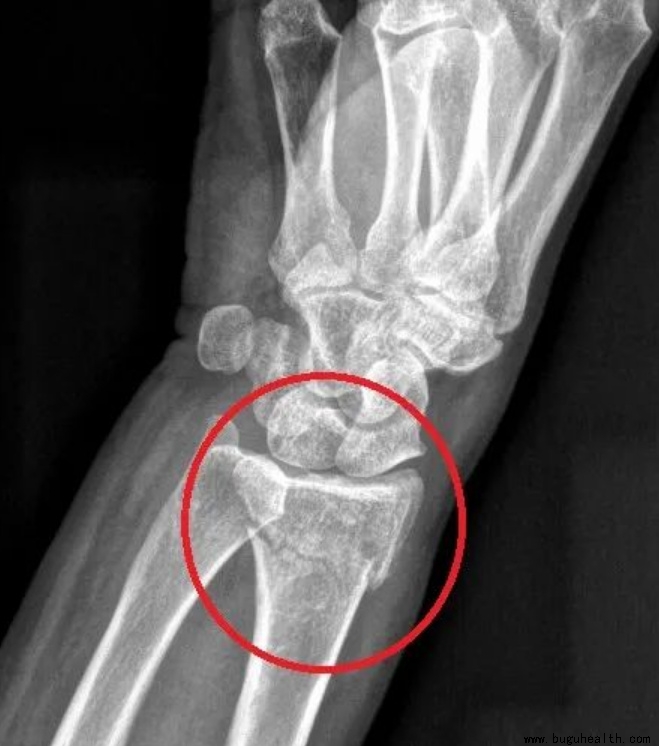

3. 桡骨远端骨折

属于手腕部的一种骨折!桡骨远端骨折是指距桡骨下端关节面3cm以内的骨折!跌倒手撑地时拇指那一侧会发生移位,严重的骨折会造成正中神经的卡压,从而引起手部肿胀、疼痛、皮下淤血。

未移位或者未涉及关节表面可保守治疗。如果桡骨远端骨折段的骨块保持对齐,没有明显的移位或错位,通常可以通过外部固定(如石膏固定或支具等外固定装置)来稳定,促使骨折部位愈合。

如果桡骨远端骨折没有涉及到关节表面,即关节面未受损,那么保守治疗的可能性也比较大。

何时可以进行康复训练?

保守治疗:在固定稳定的前提下,尽可能开展功能训练,一般石膏固定6周,期间可以活动指间关节,同时必须锻炼肩肘关节,拆除石膏后,可恢复腕关节的屈伸和旋转训练。

手术治疗:早期可开展活动和物理治疗,6-8周恢复良好可进行抗力训练,完全性功能恢复需要12-18周。